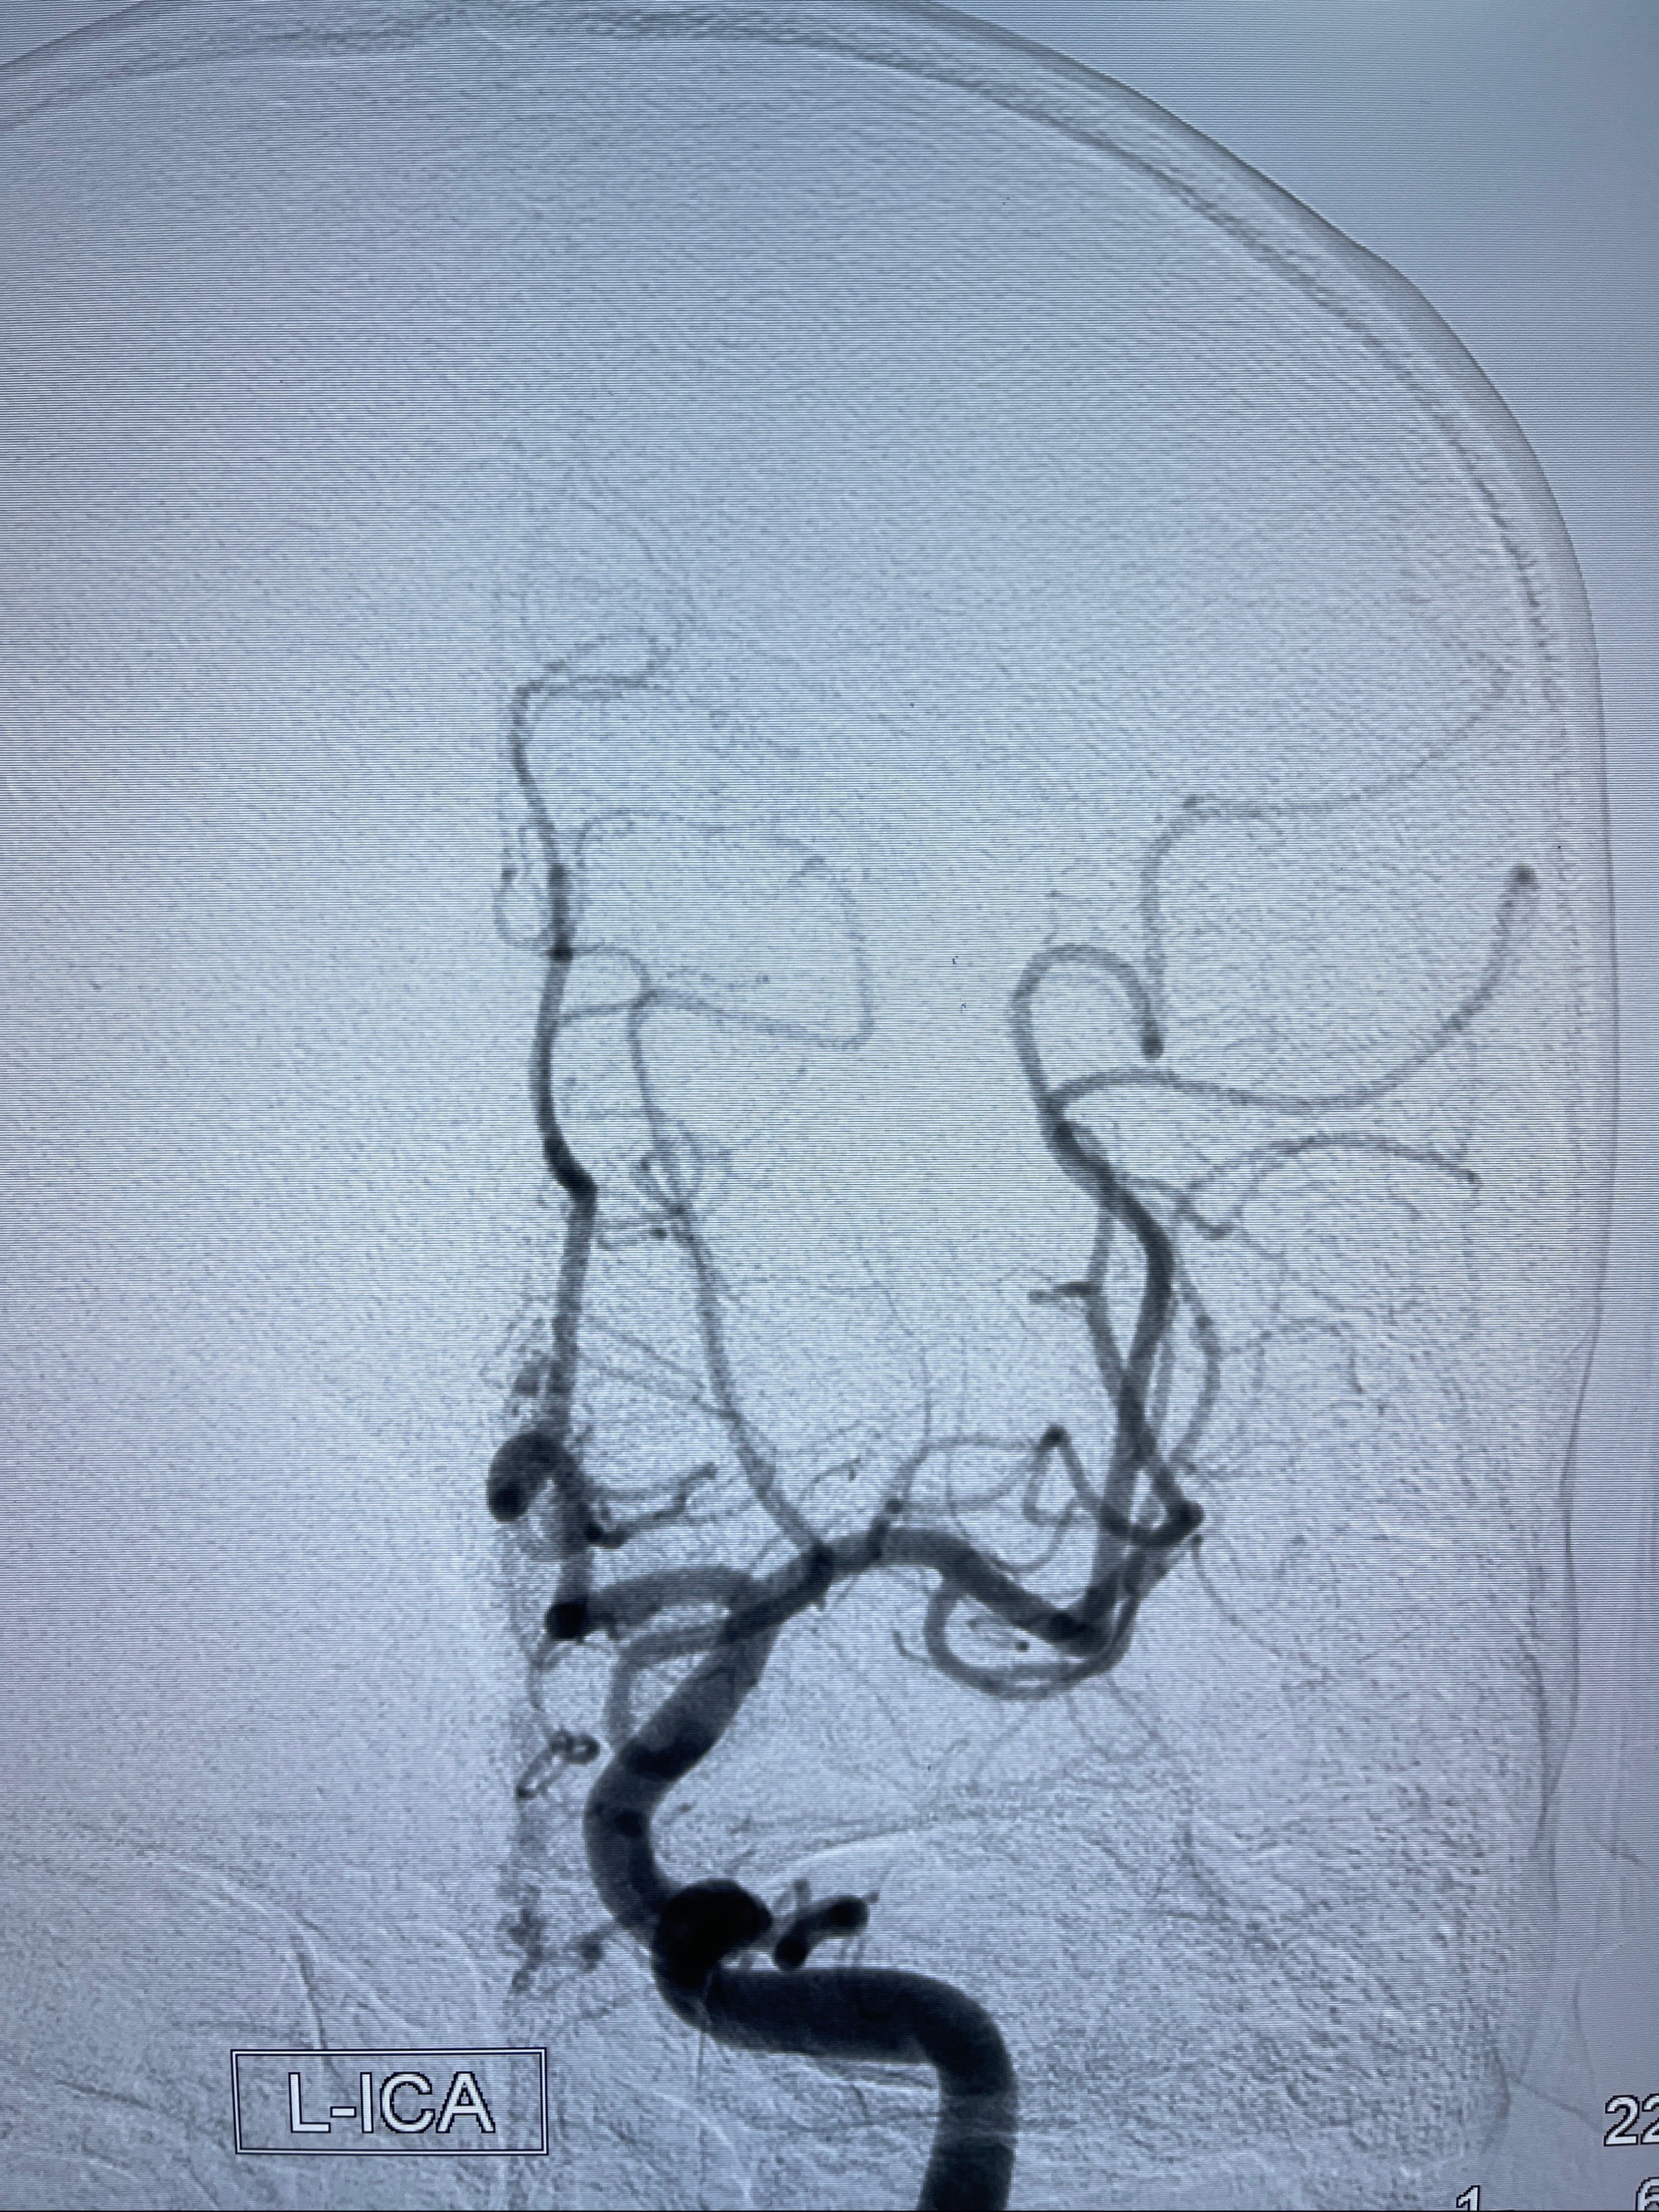

2023年8月21日]景德镇市第一人民医院脑血管造影检查,提示:主动脉弓、双侧颈总动脉、锁骨下动脉造影未见异常,左侧大脑前动脉静脉瘘。

2023-09-13全脑血管造影:前颅底硬脑膜动静脉瘘,供血动脉为双侧胼周动脉、眼动脉脑膜支,静脉向上矢状窦方向引流